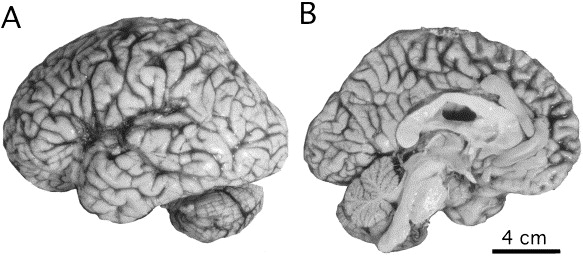

Anormal prionlar, beyin dokusunda birikerek iltihaplanmaya ve hasara yol açar, bu da beynin yapısında boşluklar oluşturarak organda süngerimsi bir görünüme neden olur. Hastalık, belirtiler başladıktan sonra hızla ilerler ve herhangi bir tedavisi bulunmadığı için maalesef ölümle sonuçlanır.

Manyetik Rezonans Görüntüleme (MRI): Hastalığa %90 oranında teşhis konulmasında etkilidir.

Beyin Dokusu Biyopsisi: Kesin tanı için nadiren başvurulan yöntemdir.